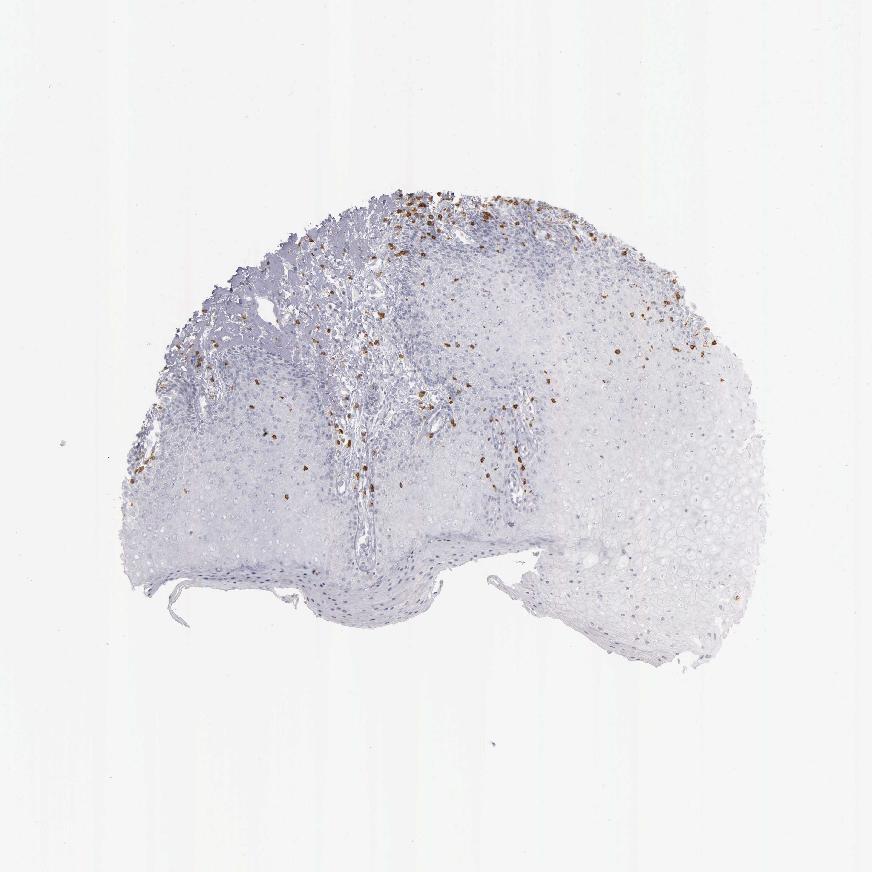

SKIN 1 - Antibody stainingi

Antibody staining in the annotated cell types in the current human tissue is reported as not detected, low, medium, or high, based on conventional immunohistochemistry profiling in selected tissues. This score is based on the combination of the staining intensity and fraction of stained cells.

Each image is clickable and will lead to virtual microscopy that enables deeper exploration of all samples and also displays staining intensity scores, fraction scores and subcellular localization as well as patient and tissue information for each sample.

Antibody HPA040957Antibody HPA043955Antibody CAB000010Antibody CAB072863Antibody CAB072864

Langerhans Not detectedNot detectedNot detectedNot detectedNot detected

Fibroblasts Not detectedNot detectedNot detectedNot detectedNot detected

Keratinocytes Not detectedNot detectedNot detectedNot detectedNot detected

Melanocytes Not detectedNot detectedNot detectedNot detectedNot detected